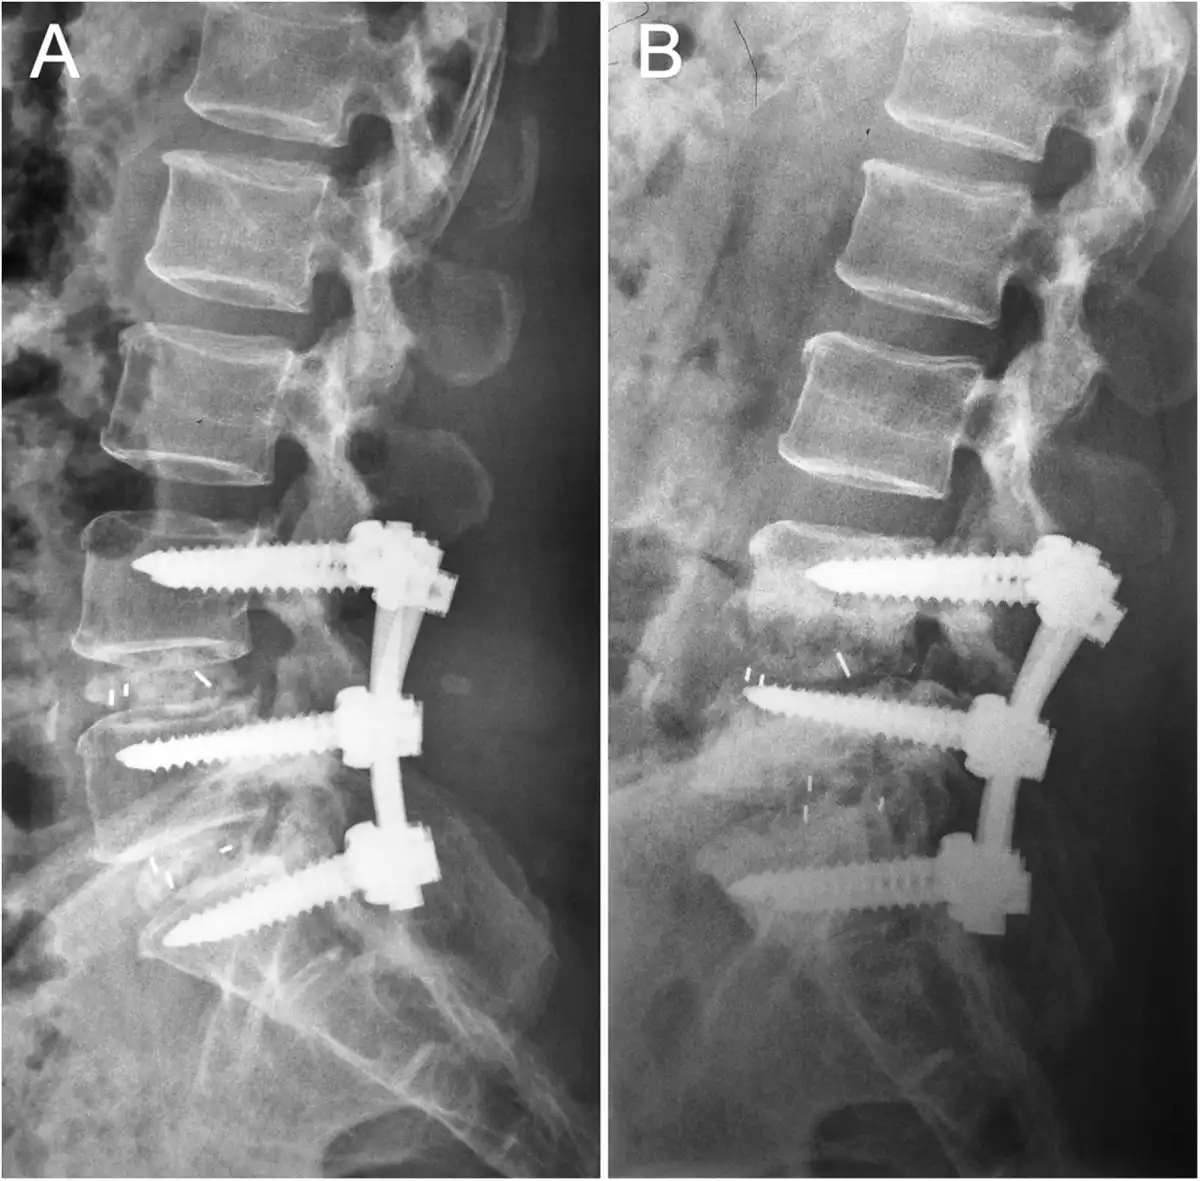

جراحی معمولاً با استفاده از پیچ و میلههای فلزی برای تثبیت مهرهها انجام میشود. این عمل بهویژه برای نوجوانانی که اسکولیوز پیشرونده دارند و بزرگسالانی که دچار درد مزمن یا ناهنجاریهای شدید شدهاند، اهمیت دارد. تشخیص دقیق و بهموقع توسط متخصص ارتوپد نقش مهمی در تصمیمگیری برای انجام جراحی دارد.

جراحی فیوژن ستون فقرات (spinal fusion) که روش استاندارد برای موارد شدید اسکولیوز است، بهبود قابل توجهی در راستای ستون فقرات و وضعیت بدنی بیماران ایجاد میکند. (منبع: Scoliosis Research Society, “New & Emerging Technologies”)